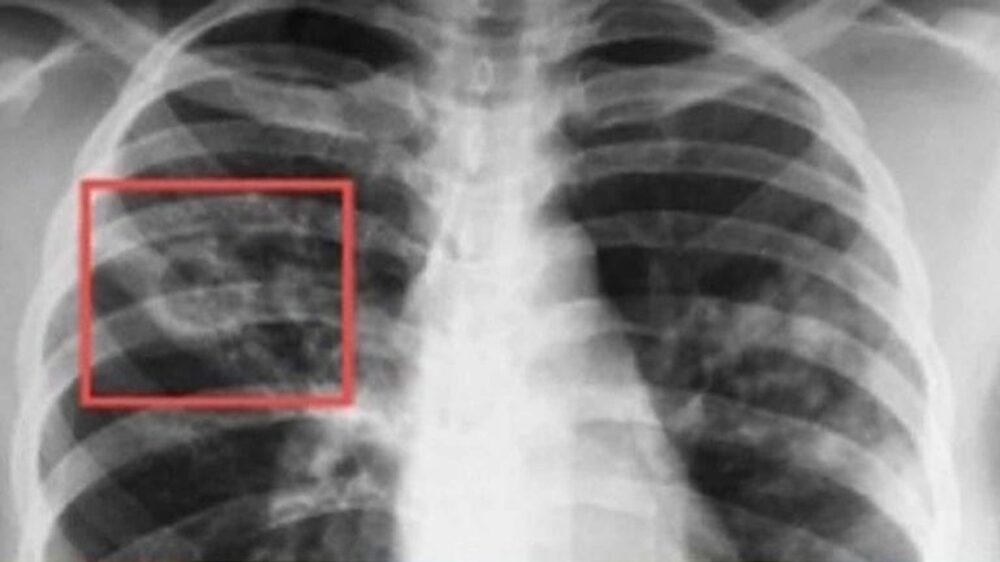

Безплатни профилактични прегледи за риск от туберкулоза ще извършват от днес, 15 септември, до петък в "Специализирана болница за активно лечение на пневмо-фтизиатрични заболявания – д-р Н. Пенчев“ - Пазарджик, съобщиха от местната администрация.

Кампанията е част от изпълнението на Националната програма за превенция и контрол на туберкулозата в Република България за периода 2021 – 2025 г. По време на „Седмицата на отворените врати“ всеки желаещ ще може да премине скрининг за риск от туберкулоза чрез анкета и медицинска консултация. При установяване на риск, ще бъдат извършени допълнителни прегледи и изследвания.